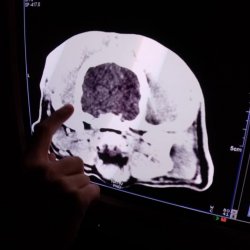

Jonášek je svěřenec dočaskářských tet. Trápila ho osina mezi prsty na přední tlapce, bohužel v jeho chlupatých nožkách nešlo nic moc vidět, a tak skončil v pondělí na veterině - poté, co mu opouzdřená osina praskla a nožka vyžadovala ošetření. Osina se ale nenašla, a tety Jonáška nechtěly bez sedace více trápit, tudíž se hned na čtvrtek domluvila sedace, v rámci které se noha chirurgicky zrevidovala, osina se našla a vytáhla. Současně se Jonášek hned vykastroval a bylo mu provedeno CT hlavy, vzhledem k jeho neurologickým příznakům a nestandartnímu chování.

CT vyšetření odhalilo, že Jonášek má velmi malý, zakrnělý mozek, jehož velikost je téměř stejná, jako velikost obou nosních dutin, tudíž se pravděpodobně jedná o vrozenou záležitost. Narozdíl od ostatních pejsků, kteří jsou zdraví, Jonáškovu větší část hlavy tvoří jen sval a podkoží. Tím bylo vysvětleno jeho zvláštní, zpomalené chování a občasná panika.Pro Jonáše budou tety hledat rodinku, kde ho přijmou takového, jaký je, nebudou po něm chtít žádné zázraky (jak říkají tety). Je to velmi hodný a klidný pejsek, který nevyžaduje žádné extra aktivní vyžití, bude mu stačit zahrádka, pohlazení a tolerantní člověkové okolo, kteří ho budou milovat. Nikdy nekousne, naučil se čistotnosti a chodí se i mazlit. S pejsky vyjde bez problémů, doma vydrží sám a neštěká, tedy, jakmile si zvykne.